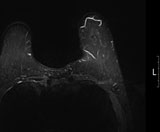

유방 MRI